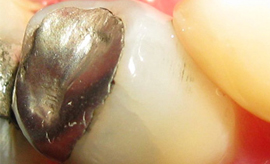

KONZERVATIVA - KOMPOZITNE ZALIVKE ![]()

Kompozitna zalivka nadomešča izgubljeno zobno strukturo (zaradi kariesa ali loma), v primerih, ko okvara na zobu ni prevelika. V preteklosti so se uporabljali neestetski materiali, kot je amalgam. Danes se amalgam skoraj ne uporablja več zaradi slabe vezi z zobom in »kovinskega« nenaravnega videza. Kompozitni materiali, ki jih uporabljamo danes, so estetski, imajo odlične mehanske lastnosti in se dobro vežejo na strukturo zob (če se uporablja pravilno).

Za zdravljenje majhnih, površinskih kariesov, popravilo majhnih defektov in nepravilnosti ter popravilo manjših estetskih nepravilnosti v obliki in barvi zob uporabljamo najmanj invazivne metode odstranjevanja kariesa s posebnimi svedri za minimalno invazivno preparacijo, ki izbrusi le karies ali odstrani staro plombo, zdrava zobovina pa ostane nedotaknjena. Takšni posegi so praviloma neboleči tudi brez anestezije. Kadar pa gre za obsežnejši karies, zlom zoba ali menjavo večje plombe nujna je obsežnejša preparacija ter bolj zapletene tehnike izdelave plomb. Pri tem uporabljamo najnovejše nadstandardne plombirne materiale, saj imajo vrsto prednosti pred klasičnimi zalivkami. So izredno obstojni, estetski ter prijazni zdravju in okolju.

Kompozitne zalivke se izdelujejo tako, da zvesto posnemajo videz naravnih zob. To pomeni, da se s pomočjo kompozitnega materiala oblikuje vsaka jamica in vršek, ki jih ima naravni zob, prehod med zobmi in zalivko pa mora biti neopazen. Na modeliranju jamiv in vrškov ne vztrajamo samo zaradi estetike, temveč tudi zaradi funkcionalnih razlogov. Vsaka zalivka ali krona z razlogom natančno posnema videz naravnih zob. Če tega ne bi upoštevali, bi prišlo do motnje pri naravni razporeditvi sil pri vgrizu, kar lahko povzroči resne zaplete v ustni votlini (izraščanje nasprotnega zoba, če je zalivka prenizka, zatikanje hrane med zobmi in krvavitev dlesni, slab zadah in nastanek žepov).

V naši ordinaciji amalgamskih zalivk ne izdelujemo. Pri njihovem odstranjevanju pa uporabljamo najvarnejše metode.